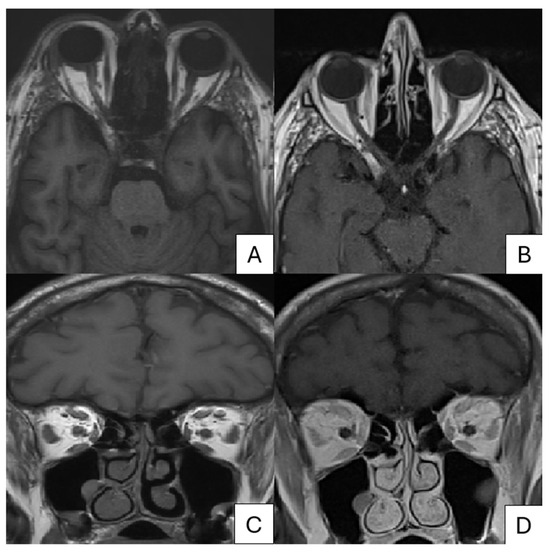

| Lee Cy et al. [12] | 78 | M | DM | Pain and swelling of the left eyelid; patchy erythema with clustered vesicles. | MRI | Left extraocular muscles (arrows) on T2; mild enhancement of the left optic nerve sheath (arrowhead), left posterior orbital wall, and left orbital apex on contrast-enhanced T1-weighted images. | Acyclovir IV + NSAIDs at first, then Acyclovir IV + Prednisolone | Limitation of abduction and paralysis of the left upper eyelid. | 6 months |